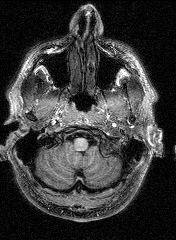

The last session involved several MRI and fMRI scans while completing tasks in the noisy environment of the scanner. Thanks to a friend who worked at the Institute, I was able to secure a copy of the raw data and an application to turn it into images, some of which are displayed here.

The images to the right are virtual 'slices', taken horizontally, starting from the top and working down. Cerebrospinal fluid is dark, the white matter appears light.